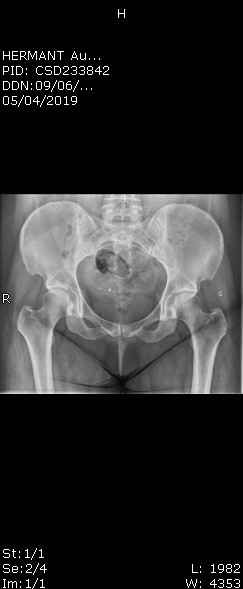

Radio de la hanche Forum Santé des adolescents;La radiographie est idéalement réalisée à l'âge de 4 mois, pour éviter les faux positifs dus à l'immaturité de la hanche Il s'agit d'une technique d'imagerie simple qui utilise des rayons X qui donne un accès rapide à l'analyse des parties osseuses du bassin et des hanches L'enfant est positionné fermement sur le dosSur la radiographie du bassin de face bien réalisée sans bascule du bassin, il existe une parfaite symétrie droite–gauche et la distance entre le sommet de la symphyse pubienne et la jonction sacrococcygienne est comprise entre 32–55 mm chez l'homme et 25–47 mm chez la femme

Une radio du bassin est indiquée La HAS rappelle que cette radio du bassin doit être parfaitement réalisée pour être interprétable incidence de face, enfant immobilisé, réduction de la lordose lombaire et pieds en rotation interne Les radios du bassin ne sont pas indiquées initialement En revanche, des radios du rachis Les faces latérales du bassin sont explorées avec la main droite pour la face droite, la main gauche pour la face gauche L'arc antérieur est apprécié dans sa forme et son épaisseur, de même que l'ogive pubienne, la saillie des épines sciatiques, la mobilité de la pédale coccygienne Évaluer la courbure du sacrum et du coccyx Attendre le défilement des explications La radiopelvimétrie Cet examen, qui peut s'effectuer soit à l'aide de radiographies standard, soit à l'aide de coupes scanner, permet de mesurer les dimensions du bassin osseux et de voir si un accouchement par voie basse est théoriquement possible

Chez le bébé Elle consiste en premier lieu en un examen clinique des hanches du bébé appelé "manœuvre de Barlow" et permet de dépister une instabilité de la hanche, confirmée par une radio du bassin • Chez l'adulte Dysplasie de la hancheLe déroulement de la radiopelvimétrie Dans certains cas, vers la fin du 8ème mois de la grossesse, on doit s'assurer par une radio ou un scanner que le bassin de la future mère est assezRéponse du Pédiatre Sur une radiographie, le noyau d'ossification de la tête fémorale peut s'apprécier à sept mois, avec des variations À l'âge de quatre mois, une radiographie permet de voir la structure du bassin et d'évaluer si la tête du fémur est bien positionnée dans l'acetabulum (cavité sphérique où elle vient se